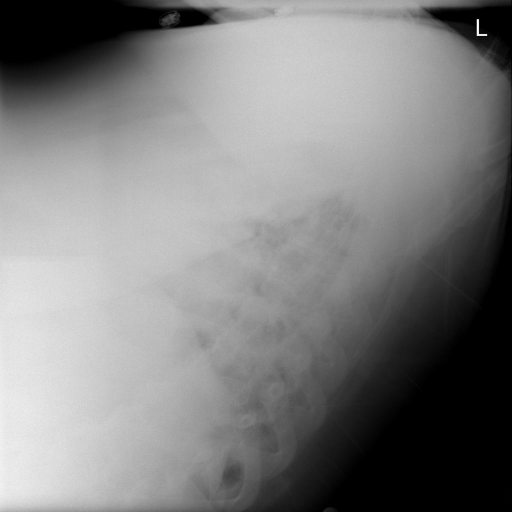

[Uncaptioned image] Generated Caption HLSTM: exam quality limited by hypoinflation and rotation. the heart is normal in size. the lungs are clear. no focal consolidation suspicious pulmonary opacity large pleural effusion or pneumothorax is identified. no pneumothorax. no acute bony abnormalities. no pleural effusion

Generated Caption HLSTM+Dual: technically limited exam. basilar probable pulmonary fibrosis and scarring. the heart is mildly enlarged. there are low lung volumes with bronchovascular crowding. there is <unk> interstitial opacity and left basal platelike opacity due to discoid atelectasis scarring. there is no pneumothorax. no large pleural effusion

GT: Stable enlarged cardiomediastinal silhouette. Tortuous aorta. Low lung volumes and left basilar bandlike opacities suggestive of scarring or atelectasis. No overt edema. Question small right pleural effusion versus pleural thickening. No visible pneumothorax.

Figure 4: Examples of generated paragraphs with our model HLSTM+Dual vs. HLSTM in comparison with the ground-truth paragraph.